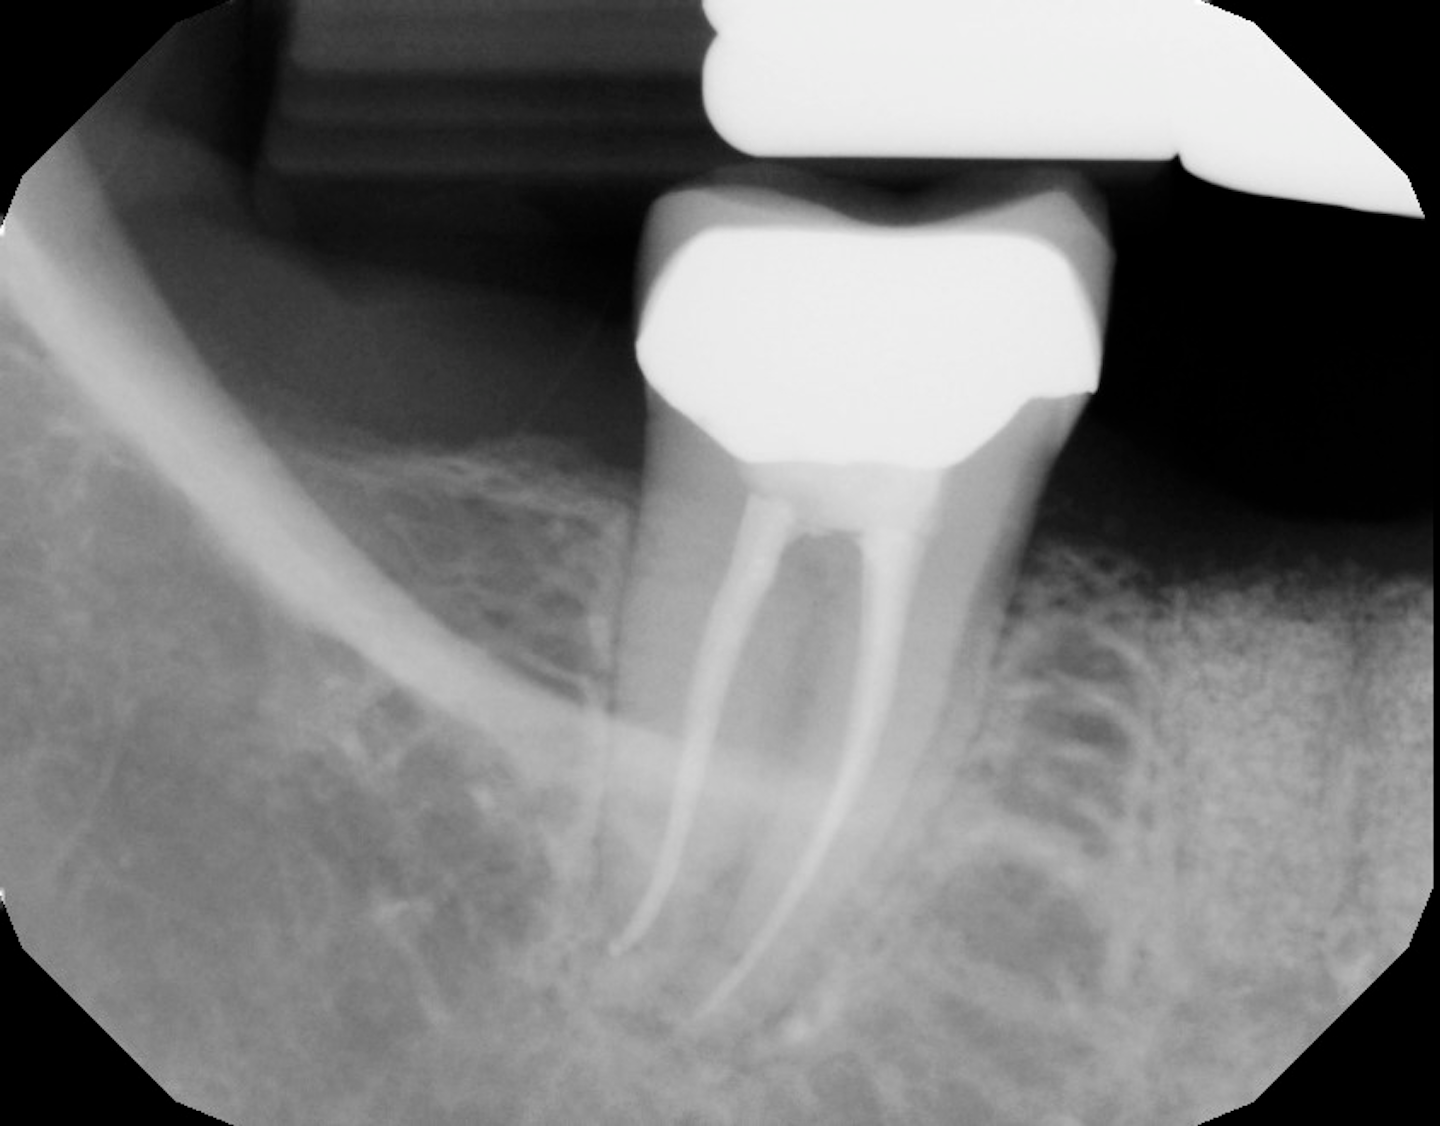

The different healing stages after a tooth extraction (with pictures)

The Different Healing Stages of a Dental Bone Graft Dental Bone Graft Blood Clot a dental bone graft is a procedure performed to increase the amount of bone in a part of the jaw where bone has been lost or where. at the same time, a blood clot forms at the interface between the graft and the recipient site to stop bleeding and release growth factors. find out how to speed. Dental Bone Graft Blood Clot.